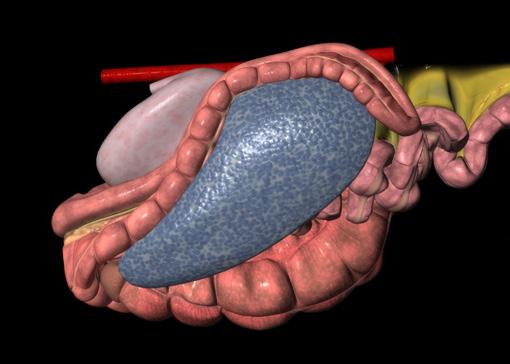

76 Reduce recurring entrapment colic

Jackie Bellamy-Zions talks to Dr. Nicola Cribb about new research showing how preventative surgery can reduce the risk of recurrent nephrosplenic entrapment colic in horses.

THE KING CHARLES III STAKES (5f ) | £700,000